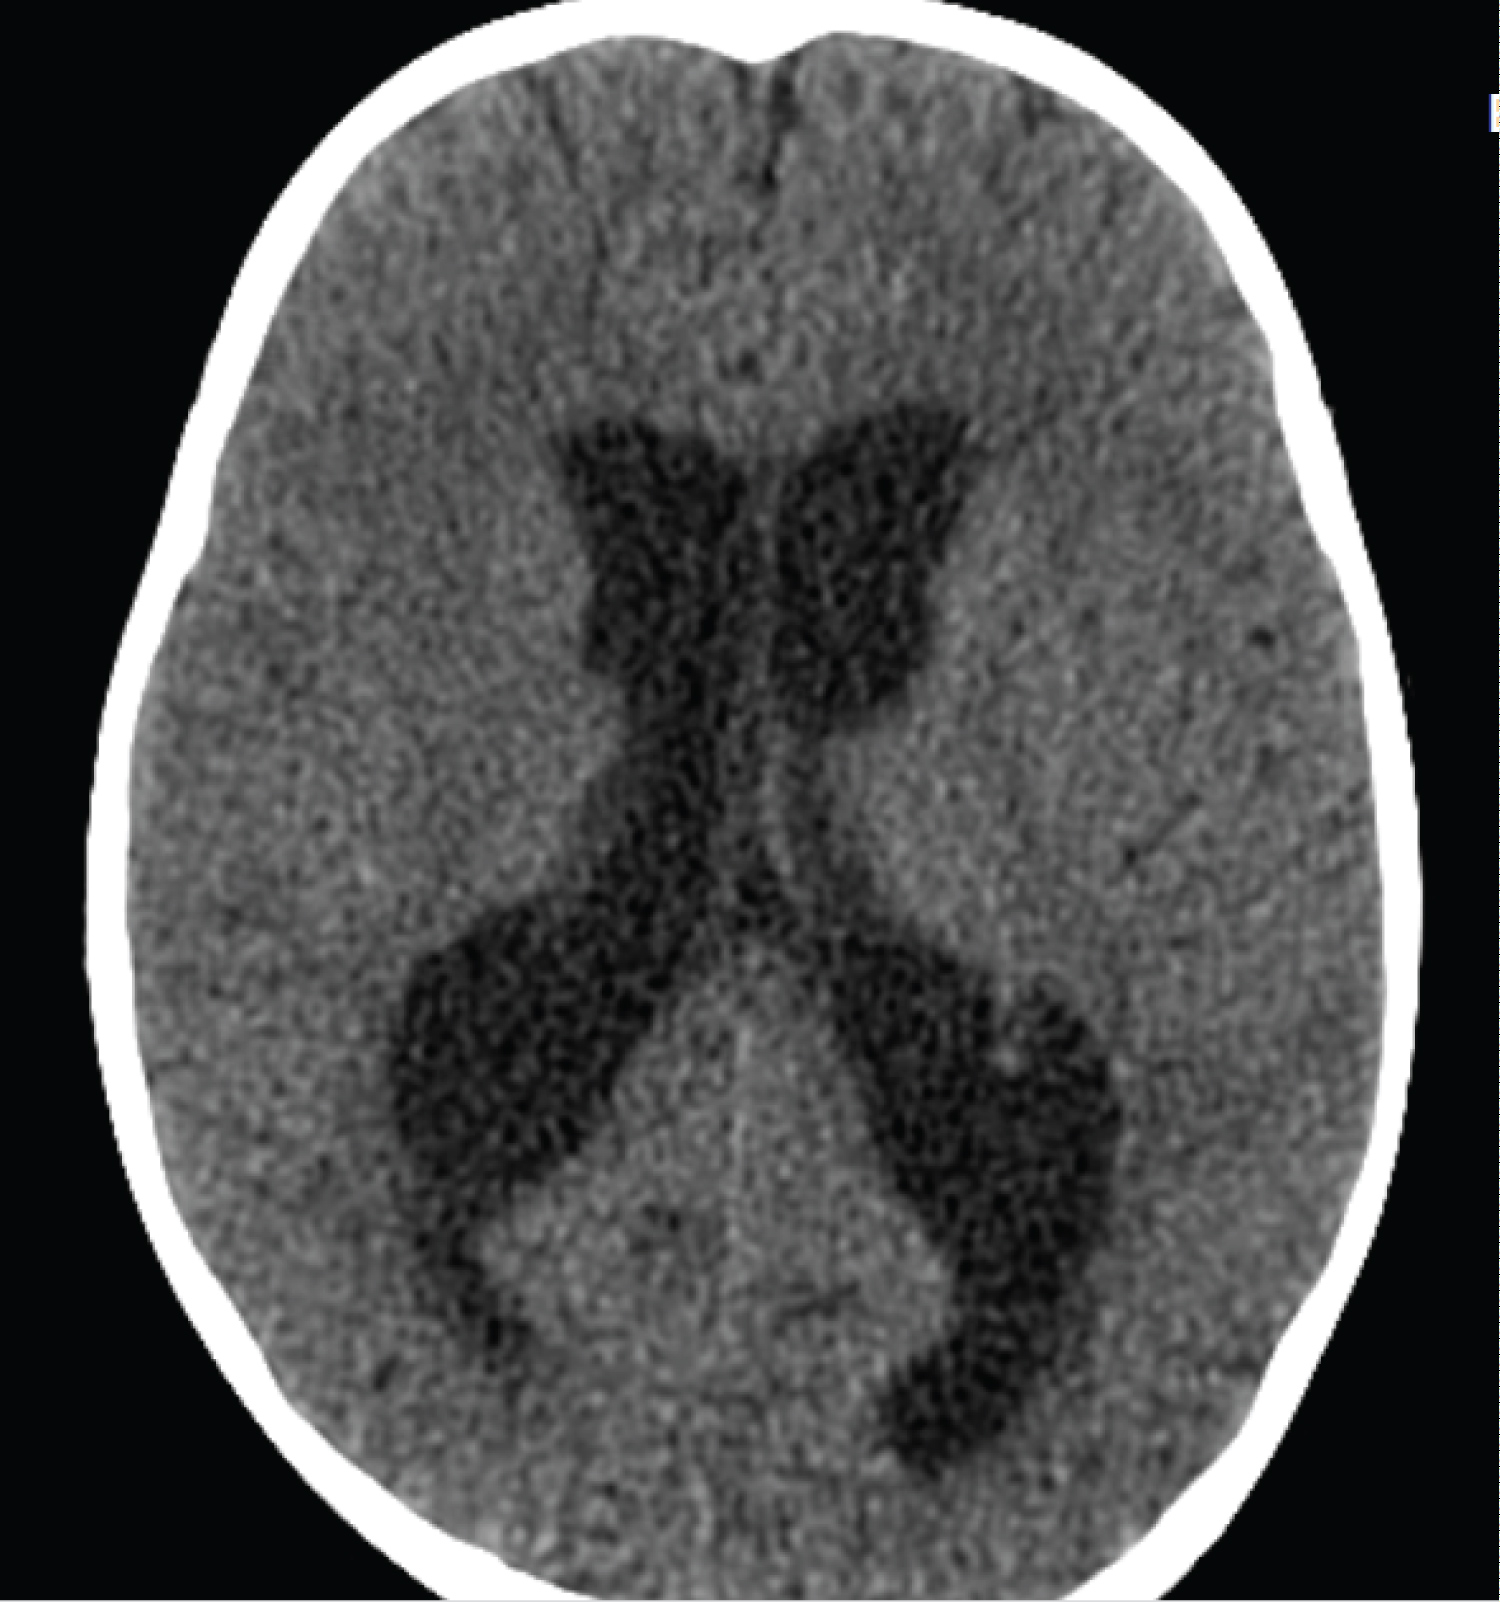

The patient is a 2-year-old child who referred to the pediatric emergency room due to loss of consciousness and suspected seizure symptoms. Also, the child's COVID-PCR test was reported positive 12 days before the visit, and the child had symptoms of cough and mild fever at the same time, which recovered at the same time. At the time of visit, the child was sleepy. He opened his eyes with painful stimulation and moved his right limbs less. Pupils were mid-sized, reactive and symmetrical. In the following examinations, there was no deviation in the eyes. Gag and corneal reflexes were normal. The child had spontaneous breathing and blood pressure and heart rate were normal. In the continuation of the history of the child, intolerance to food and milk was also mentioned. The initial blood sugar of the child was normal. After performing the initial measures, due to the unavailability of MRI, the child was subjected to brain CT scan. In the initial CT scan, the large size of the cerebral ventricles and hydrocephalus were mentioned for the child (Figure 1, Figure 2, Figure 3, Figure 4, Figure 5 and Figure 6). Due to hydrocephalus and clinical signs of increased ICP, the child was urgently transferred to the operating room, and while measuring ICP and sending a CSF sample, a ventriculoperitoneal shunt was implanted for the child. The child's icp was measured at 32 cmH2O. After the surgery, the child's level of consciousness improved relatively. The variables of the CSF sample sent were all in the normal range. The next day, the child underwent brain MRI and MRA. In the performed MRI, a clear signal change was seen in the frontal and occipital lobes, which is shown in photos No. 2, 3, 4, 5 and 6. According to the MRI, a biopsy was taken from the child's right frontal lobe for a definitive diagnosis. Immunohistochemical examination revealed the demyelinating nature of the specimen, in which extensive infiltration of basal macrophages and activated microglial cells was seen, while axons were largely preserved. No sign of vasculitis was seen in the examination of the sample. In this way, the result of the examination of the brain sample confirmed ADEM. With this diagnosis, the child was treated with corticosteroids and IVIG. The disease responded dramatically to the treatment. All the child's symptoms improved within two days and the child's level of consciousness reached its normal range. Finally, the child was discharged from the hospital after a week with a good general condition.

Figure 1: Axial computed tomography image showing hydrocephalus. View Figure 1